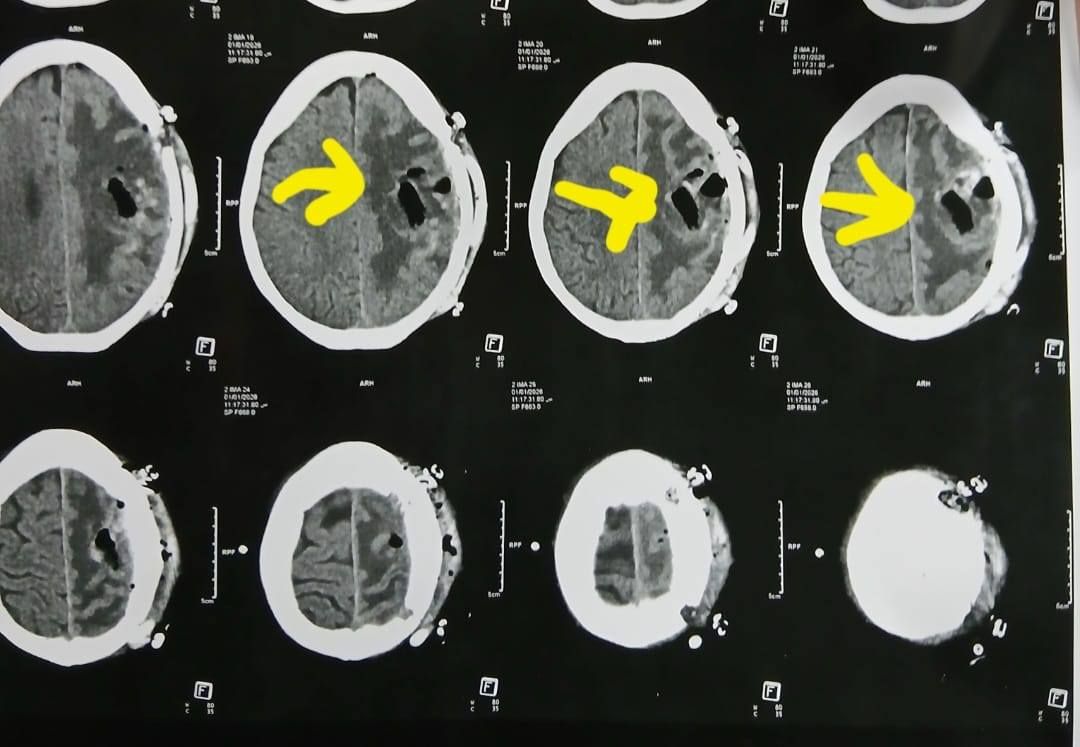

وكشف الدكتور إبراهيم الغريب رئيس قسم جراحة المخ والأعصاب بالمستشفى، أنه تعود تفاصيل الحالة إلى استقبال المستشفى المريضة بالعيادة الخارجية وهي تشكو من تنميل وضعف بالجانب الأيمن وثقل بسيط في الكلام، وبإجراء الفحوصات اللازمة من أشعة مقطعية ورنين مغناطيسي بالصبغة، تبين وجود ورم بالمخ، وتم إعطاؤها العلاج المناسب لحين استكمال الفحوصات.

أشعة المريضة

الأشعة الخاصة بالمريضة

الأشعة